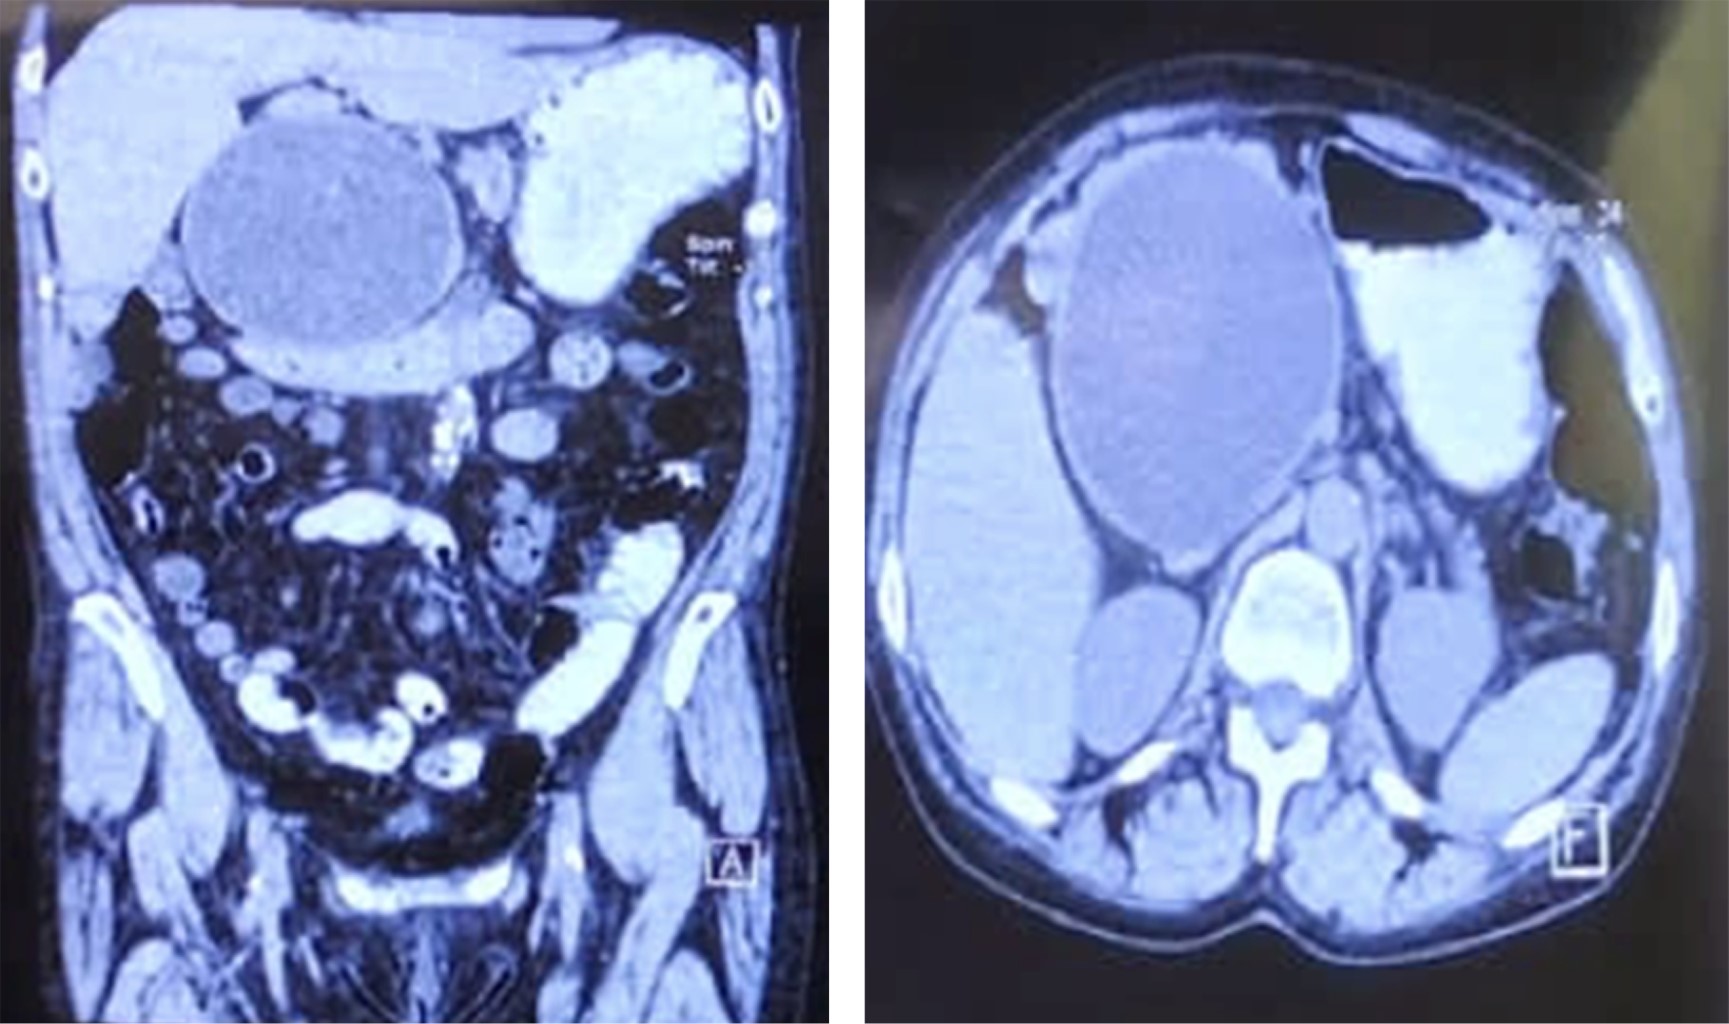

Femenino de 61 años de edad, con antecedente de pancreatitis aguda (no litiásica) en 2018. En enero de 2023 presentó cuadro de dolor abdominal localizado en cuadrante superior derecho, intensidad 4/10, con tumoración palpable no dolorosa. Se realizó ultrasonido (US) endoscópico y tomografía computarizada (TC) abdominal con presencia de pseudoquiste pancreático gigante con medidas de 15 × 15 cm y volumen de 350 cm3 (Figura 1). Se comentaron las opciones a la paciente de acuerdo con el tratamiento y se realizó cistogastroanastomosis laparoscópica y drenaje de 300 cm3 de material purulento (Figura 2), se creó ventana gástrica y anastomosis con puntos intracorpóreos sin incidentes (Figura 3). Presentó adecuada evolución, inició vía oral al segundo día y egresó a domicilio al quinto día sin complicaciones.

Figura 1